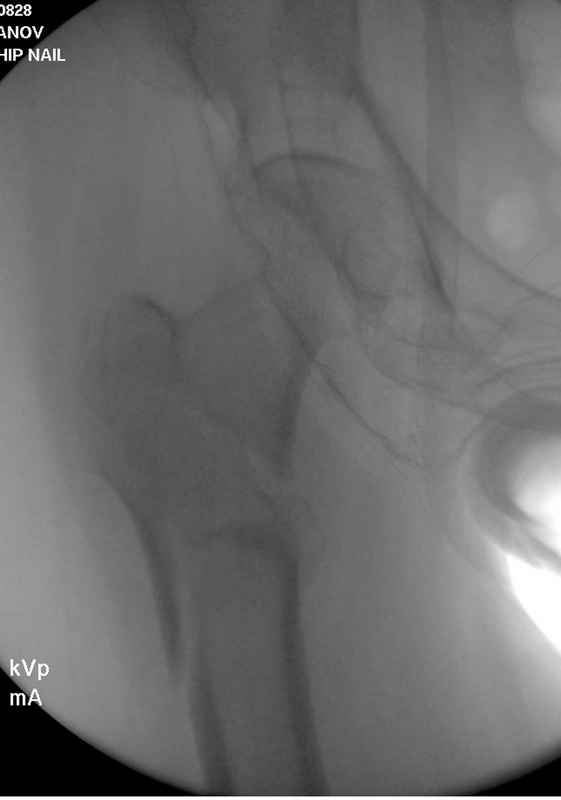

[Ortho] Чрезвертельный перелом бедра

Здесь 83 года, травма в результате падения

Имя     : #5 IT fx  2introp.jpg